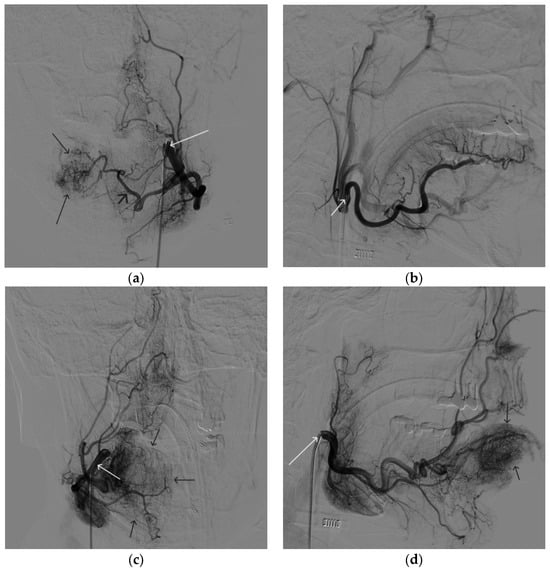

A 58-year-old male patient was admitted to the clinic complaining of a palpable formation in the left submandibular region. When angiography was performed, the filling of the vascular network of the tumor of the left submandibular region from the branches of the left occipital artery, as well as the muscular branches of the left vertebral artery, was noted (Figure 11). The patient underwent intravascular embolization of the paraganglioma with 7.5 mL of non-adhesive composition ONYX18 (Figure 12 and Figure 13). The vascular network supplying the paraganglioma was partially switched off (Figure 14). There were no complications. The mRs score at discharge was 1.

Figure 11. Digital subtraction angiography from the left common carotid artery: (a) direct projection, (b) lateral projection (white arrows indicate the left internal carotid artery, long black arrows indicate the external carotid artery, short black arrows indicate the boundaries of the paraganglioma).

Figure 12. Distribution of ONYX18 along the vascular network of the paraganglioma: (a) direct projection, (b) lateral projection (white arrows indicate filling of the vascular network of the paraganglioma, black arrows indicate an inflated balloon in the left internal carotid artery).

Figure 13. X-ray in single shot mode. (ac) Demonstration of gradual spreading of ONYX18 (NAGLEMs cast) through the vascular network of the paraganglioma direct projections (black arrows indicate filling of the vascular network of the paraganglioma, white arrows indicate an inflated balloon in the left internal carotid artery).

Figure 14. Digital subtraction angiography from the left common carotid artery: (a) direct projection, (b) lateral projection (white arrows indicate the guiding catheter in the left external carotid artery, black arrows indicate the boundaries of the embolized paraganglioma).